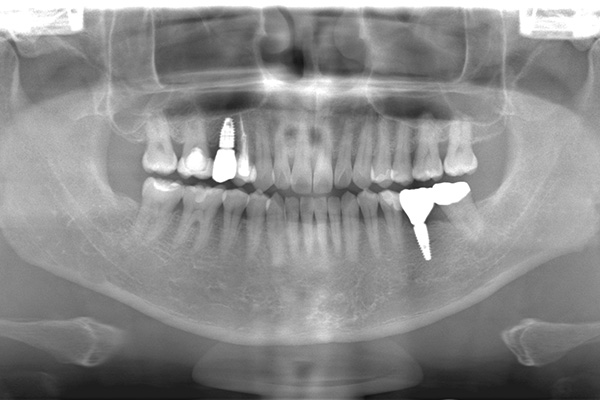

インプラントの症例 インプラントの症例

治療前〜治療後のレントゲン写真

患者様の要望奥歯にインプラント治療したい

治療期間4ヶ月

治療費用880,000円

治療内容左上奥歯に2本インプラント埋入

治療のリスクネジが緩む可能性あり